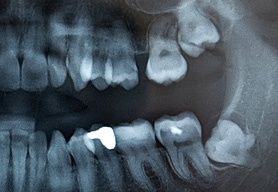

2. Nicht selten wird die Vermutung geäußert, dass die Weisheitszähne die anderen Zähne verschieben würden. Diese Hypothese trifft auf die Zähne im Unterkiefer zu. Dort sitzen die Zahnkeime im Kieferwinkel und können, wenn „es zu eng ist“, beim Wachsen nach oben durch ihre Keilwirkung eine große Kraft entwickeln. Diese Kraftentwicklung ist direkt vom Wurzelwachstum dieser Zahnanlagen abhängig. Ist das Wurzelwachstum abgeschlossen, gibt es durch diese Zähne keine Verschiebungen mehr. Die Verschiebungen werden neben einer Verlagerung des Weisheitszahnes selbst, in der seitlichen Zahnreihe auf der selben Seite beobachtet. Besteht kein Kontakt zwischen schiebendem Zahnkeim und verschobenem Nachbarzahn, so liegen andere Gründe für die beobachtete Zahnwanderung vor. Ein Nachweis dieser Situation ist durch eine Röntgenschichtaufnahme vom Unterkiefer (OPT) leicht zu erbringen. Eine Verschiebung der Zähne im Oberkiefer ist durch die Weisheitszähne nicht möglich. Auf Grund der fehlenden Keilwirkung kann hier keine Kraft entstehen, die die Zähne in der Oberkieferzahnreihe verschieben könnte. Der wachsende Zahnkeim weicht nach distal (rückwärts) aus. Kommt es dennoch zu Zahnverschiebungen im Oberkiefer, sind auch hier andere Mechanismen dafür verantwortlich.

4. Aus den gleichen Gründen, wie oben unter 3. geschildert, ist auch die Pflege dieser Zähne erschwert oder sogar unmöglich. Dies gilt gleichermaßen für Patient und Zahnarzt! Ist ein verlagerter Weisheitszahn von Karies befallen, kann dies lange unentdeckt bleiben. Der kranke Zahn kann auf den gesamten Organismus im Sinne eines Herdgeschehens eine schädliche Wirkung entfalten. Nicht immer gelingt es, dieser Situation mit der Röntgendiagnostik gerecht zu werden. Oftmals läßt sich die pathologische (krankmachende) Wirkung eines solchen Herdgeschehens erst im Nachhinein (retrospektiv), wenn der schuldige Zahn eine geraume Zeit aus dem Kiefer entfernt worden ist, belegen.